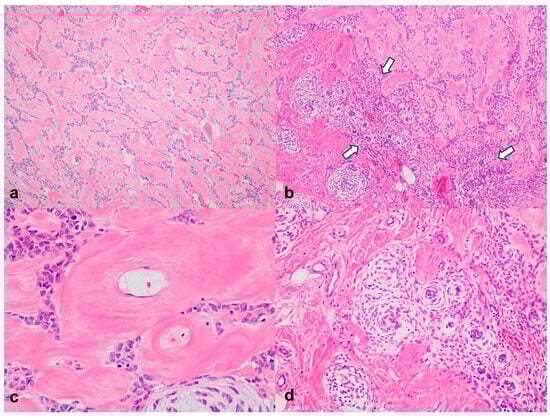

3.2. Histopathological Results